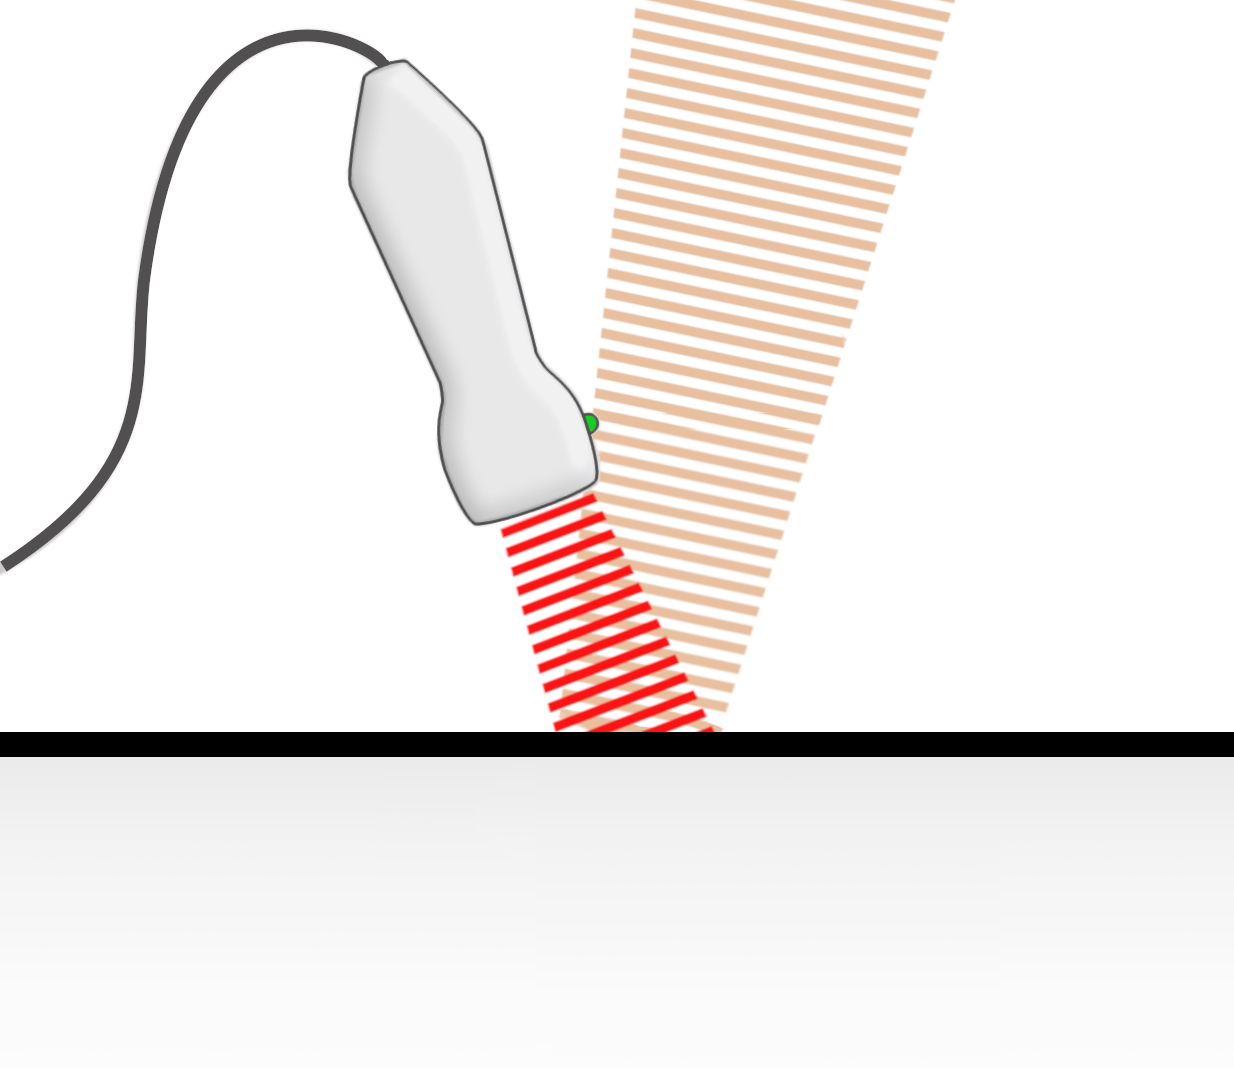

können gebrochen werden (= Refraktion)

Schallbrechung

es kommt zur Richtungsänderung beim Übergang von Schallwellen in ein Medium mit anderer Schallgeschwindigkeit